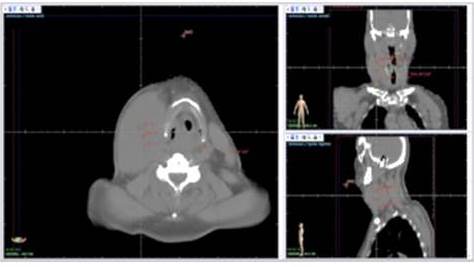

Utilizamos un sistema de planificación de tratamiento computarizado MIRS versión 6 (Figura 1). Se elaboró un primer plan, por 9 campos, 5 oblicuos, dos laterales, uno anterior y uno posterior, del cual se entregaron 4 320 cGy en 36 fracciones de 120 cGy por fracción (Figura 2).